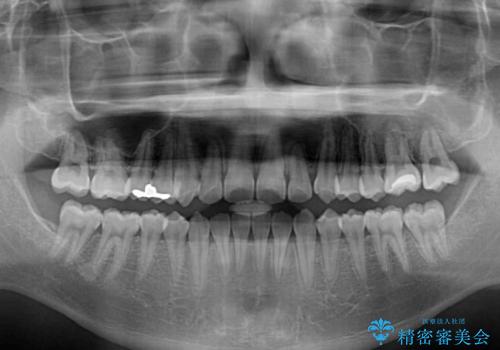

非抜歯ワイヤー装置による、短期間での矯正治療

- 上下前歯のデコボコを気にして来院された患者様です。

ワイヤー矯正でもマウスピース矯正でも可能でしたが、短期間で、自身の手を煩わせることなく治療を行いたいとのことで、ワイヤー装置にて矯正治療を行うこととしました。

当初予定通り、1年間で治療を終えることができました。